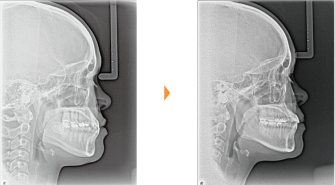

| 主訴 | 上の前歯が出ている、下の前歯がデコボコ |

| 年齢・性別 | 26歳 / 女性 |

| 治療方針 | 顎関節に少し問題があるAngleⅠ級上下顎前突。患者の希望もあり、できるだけ前歯を後退して口元の突出感の改善を行う。 |

| 抜歯部位 | 小臼歯4本抜歯 |

| 使用装置 | ホールディングアーチ、マルチブラケット装置 |

| 治療期間 | 26か月 |

| リテーナー | 上顎インビジブル、下顎スプリングリテーナー |

| 費用 | 825,000円(税別) |